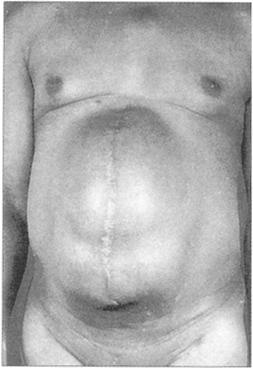

4.其他腹壁疝(图223)

图223 腹外疝

下面2幅图显示了疝缺损的变化巨大双侧腹股沟疝(图224);切口疝(图225)。

图225 切口疝